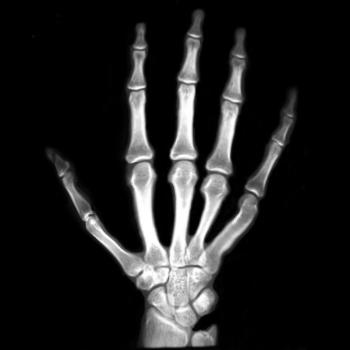

Figure 7. The first hand X-ray example.

7.2. Real X-ray images

After testing our proposed method on several synthetic images, we now consider applying it on real medical images. Here, we consider a hand X-ray image as the source image (Fig. 7(a)) and a deformed hand X-ray image as the target image (Fig. 7(b)). Fig. 7(c) shows the original absolute intensity difference between the two images. It can be observed that different fingers are displaced in a nonuniform manner (for example, the displacement of the index finger is much larger than that of the little finger), while the wrist remains almost the same. Therefore, a simple rigid transformation is insufficient for yielding a good registration. As shown in Fig. 7(d), our proposed method successfully deforms the source image to match the target image, and the final intensity difference is significantly smaller (see Fig. 7(e)). From the deformed underlying grid in Fig. 7(f), it can be observed that the mapping is smooth and bijective. For comparison, both LDDMM [5] and DDemons [47] fail to register the fingers and are non-bijective (see Fig. 7(g), Fig. 7(h), and Fig. 7(i)).